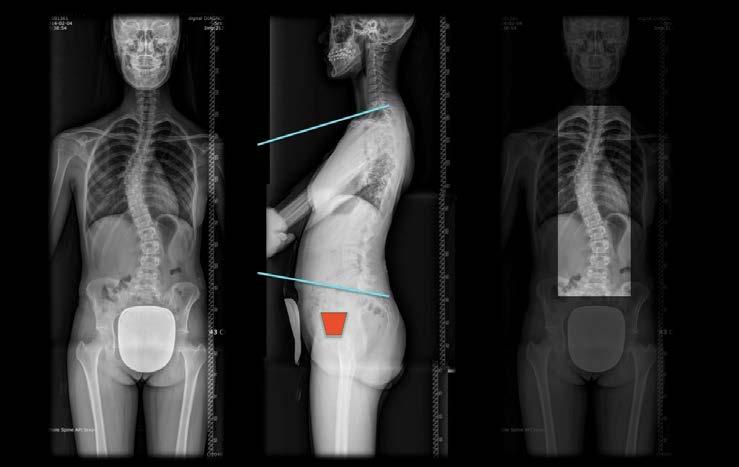

Um eine Skoliose zu diagnostizieren, benötigt man ein Röntgenbild. Es sollte zur Verlaufskontrolle möglichst eine Wirbelsäulenganzaufnahme im Stehen (Abbildung 49) angefertigt werden, beim ersten Mal von vorne bzw. hinten und von der Seite. Auf der Aufnahme von vorne kann man den Krümmungswinkel messen und erkennen, ob Rippen- oder Wirbelfehlbildungen vorliegen. Man sichert somit beispielsweise die Diagnose einer idiopathischen Skoliose oder im Falle vorliegender Wirbel- oder Rippenfehlbildungen die Diagnose einer angeborenen Skoliose. Auf der Aufnahme von der Seite erkennt man, ob in dieser Ebene Wirbelfehlbildungen vorliegen oder ob im Bereich der Brustwirbelsäule ein Hohlrücken besteht. Ein solcher Hohlrücken ist für die Prognoseerstellung von Bedeutung. Röntgenaufnahmen dieser Art und Größe stellen natürlich eine gewisse Strahlenbelastung dar. Dennoch kann man nicht auf sie verzichten. Röntgenaufnahmen sind immer dann erforderlich, wenn nach klinischen Messungen eine Verschlechterung zu erwarten ist oder auch zur Überprüfung einer Korsettversorgung. Nach den ersten Aufnahmen zur Diagnosestellung ist jedoch eine Seitaufnahme in der Regel nicht mehr erforderlich. Des Weiteren kann zur Einsparung der Strahlendosis eine sogenannte „low dose“-Aufnahme durchgeführt werden, mit entsprechender Verkürzung der Belichtungszeit und weitgehender Einblendung, sofern es nur um das Ausmessen des Krümmungswinkels geht. Leider bleibt diese strahlensparende Aufnahme nur schlanken Patienten vorbehalten.

79 Abbildung 49: Wirbelsäulenganzaufnahme einer Patientin mit Idiopathischer Skoliose. Unnötigerweise sieht man den Kopf und große Teile des Oberschenkels auf den Bildern. Auch fehlt auf der Seitaufnahme in der Mitte der Strahlenschutz. Rechts ist der Teil des Röntgenbildes markiert, der in der Regel ausreicht, um die Skoliose richtig zu diagnostizieren und den Krümmungswinkel zu messen (ROI = Region of Interest). Wenn man sich beim Röntgen auf die ROI beschränkt, kann man die Strahlenbelastung drastisch reduzieren. LESEPROBE